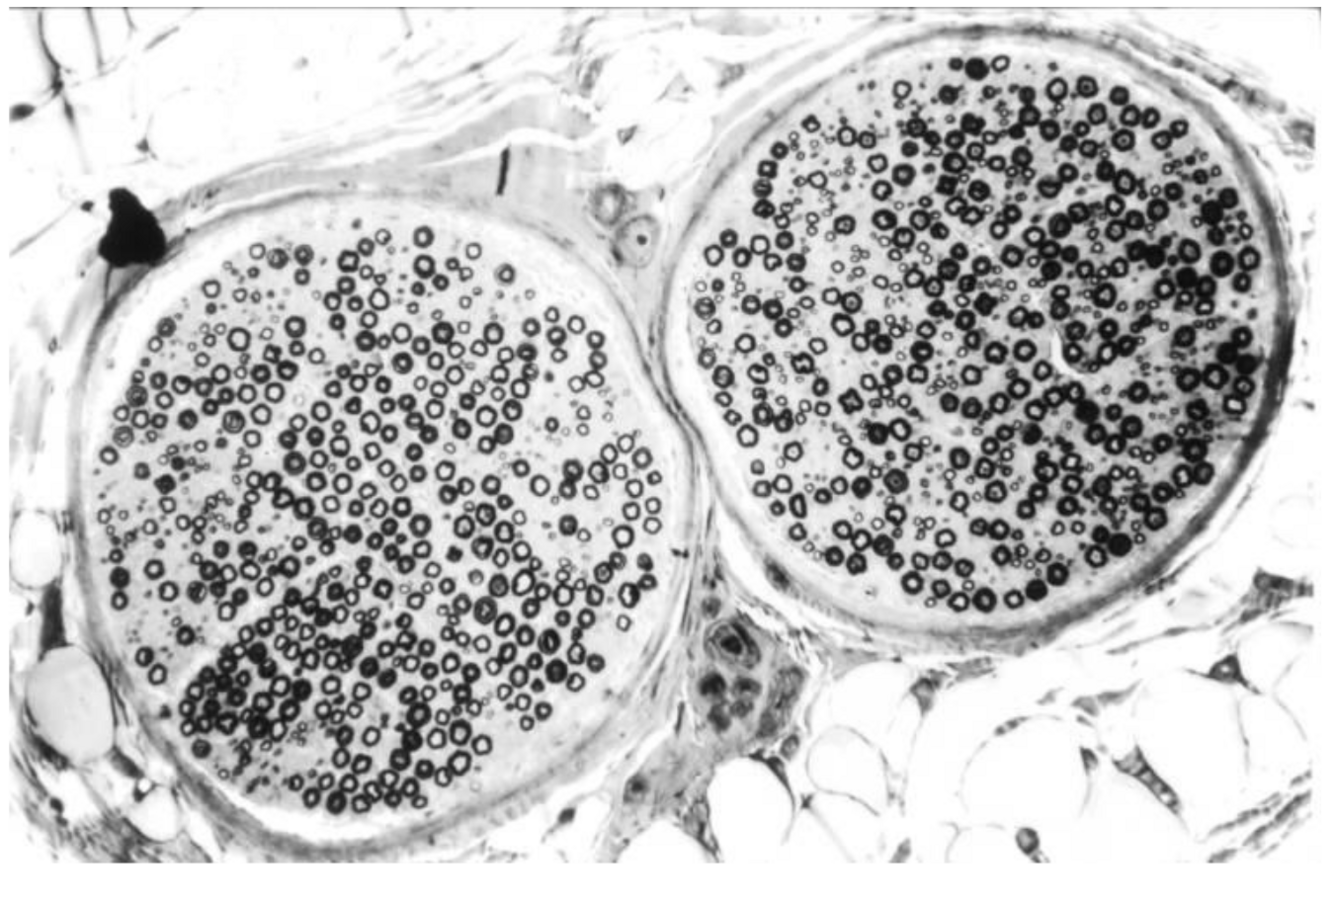

What can be seen in the image below?

Nerve fascicle, TS, HE stain

Each fascicle has a very particular structure.

Myelinated and unmyelinated nerve fibers.